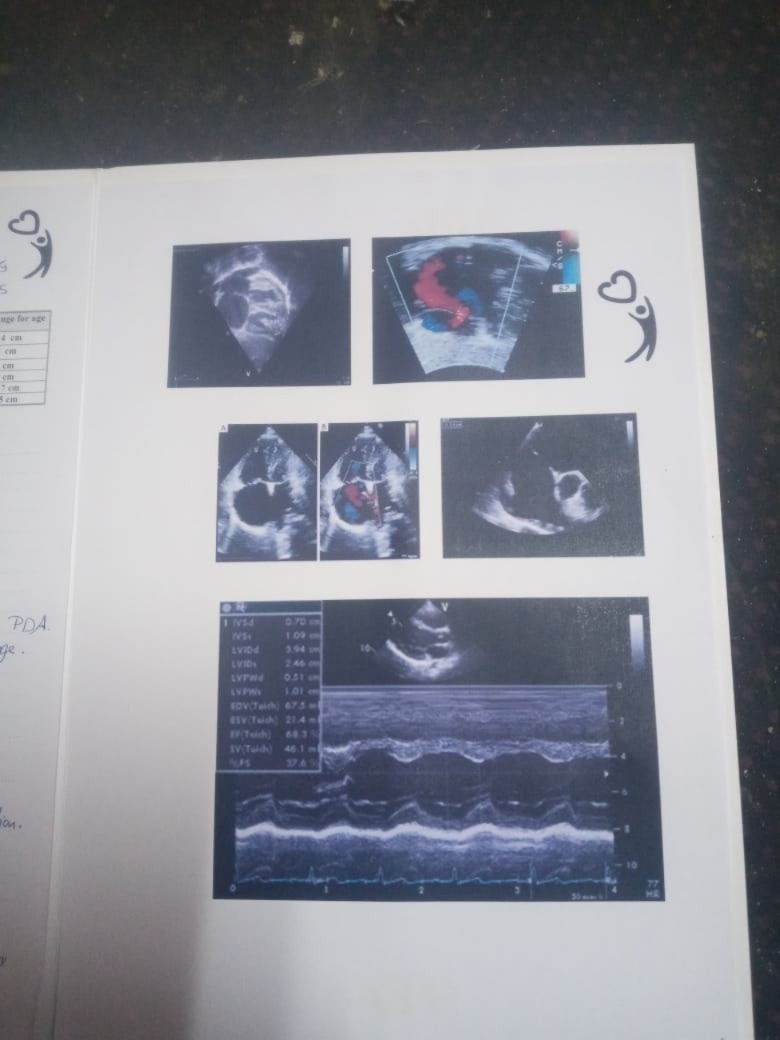

وقال الدكتور جمال شعبان، في تصريحات خاصة لـ القاهرة 24: التشخيص الخاص بحالة الطفل آدم حديث الولادة والذي يعاني من مشكلة صحية بالقلب هو Hypo plastic left ventricle، وهذه الحالة المرضية عبارة عن ضمور خلقي وراثي في البطين الأيسر، وحلول العلاج مؤقتة.